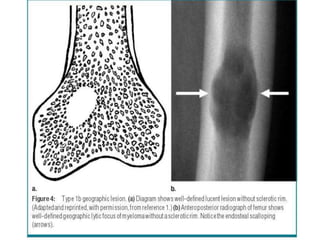

Geographic Pattern

Radiological Findings • Exactlocation of the tumour • Borders of the tumour • Pattern of bone destruction • Matrix formation/mineralization • Periosteal reaction